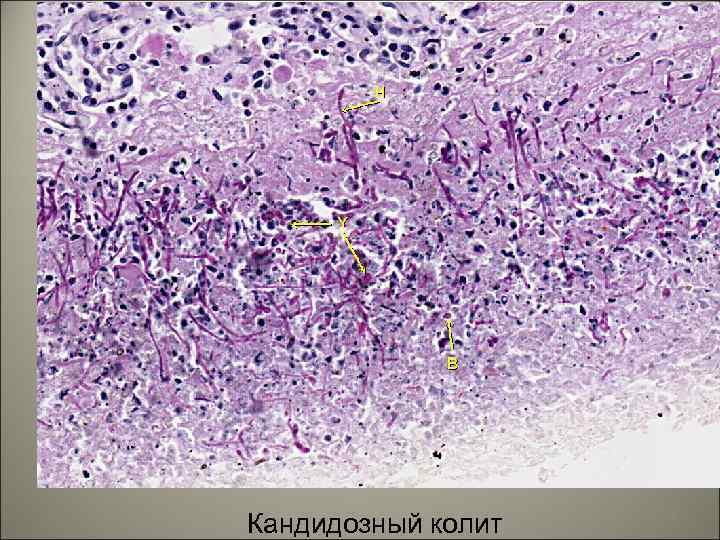

Кандидозный колит 58